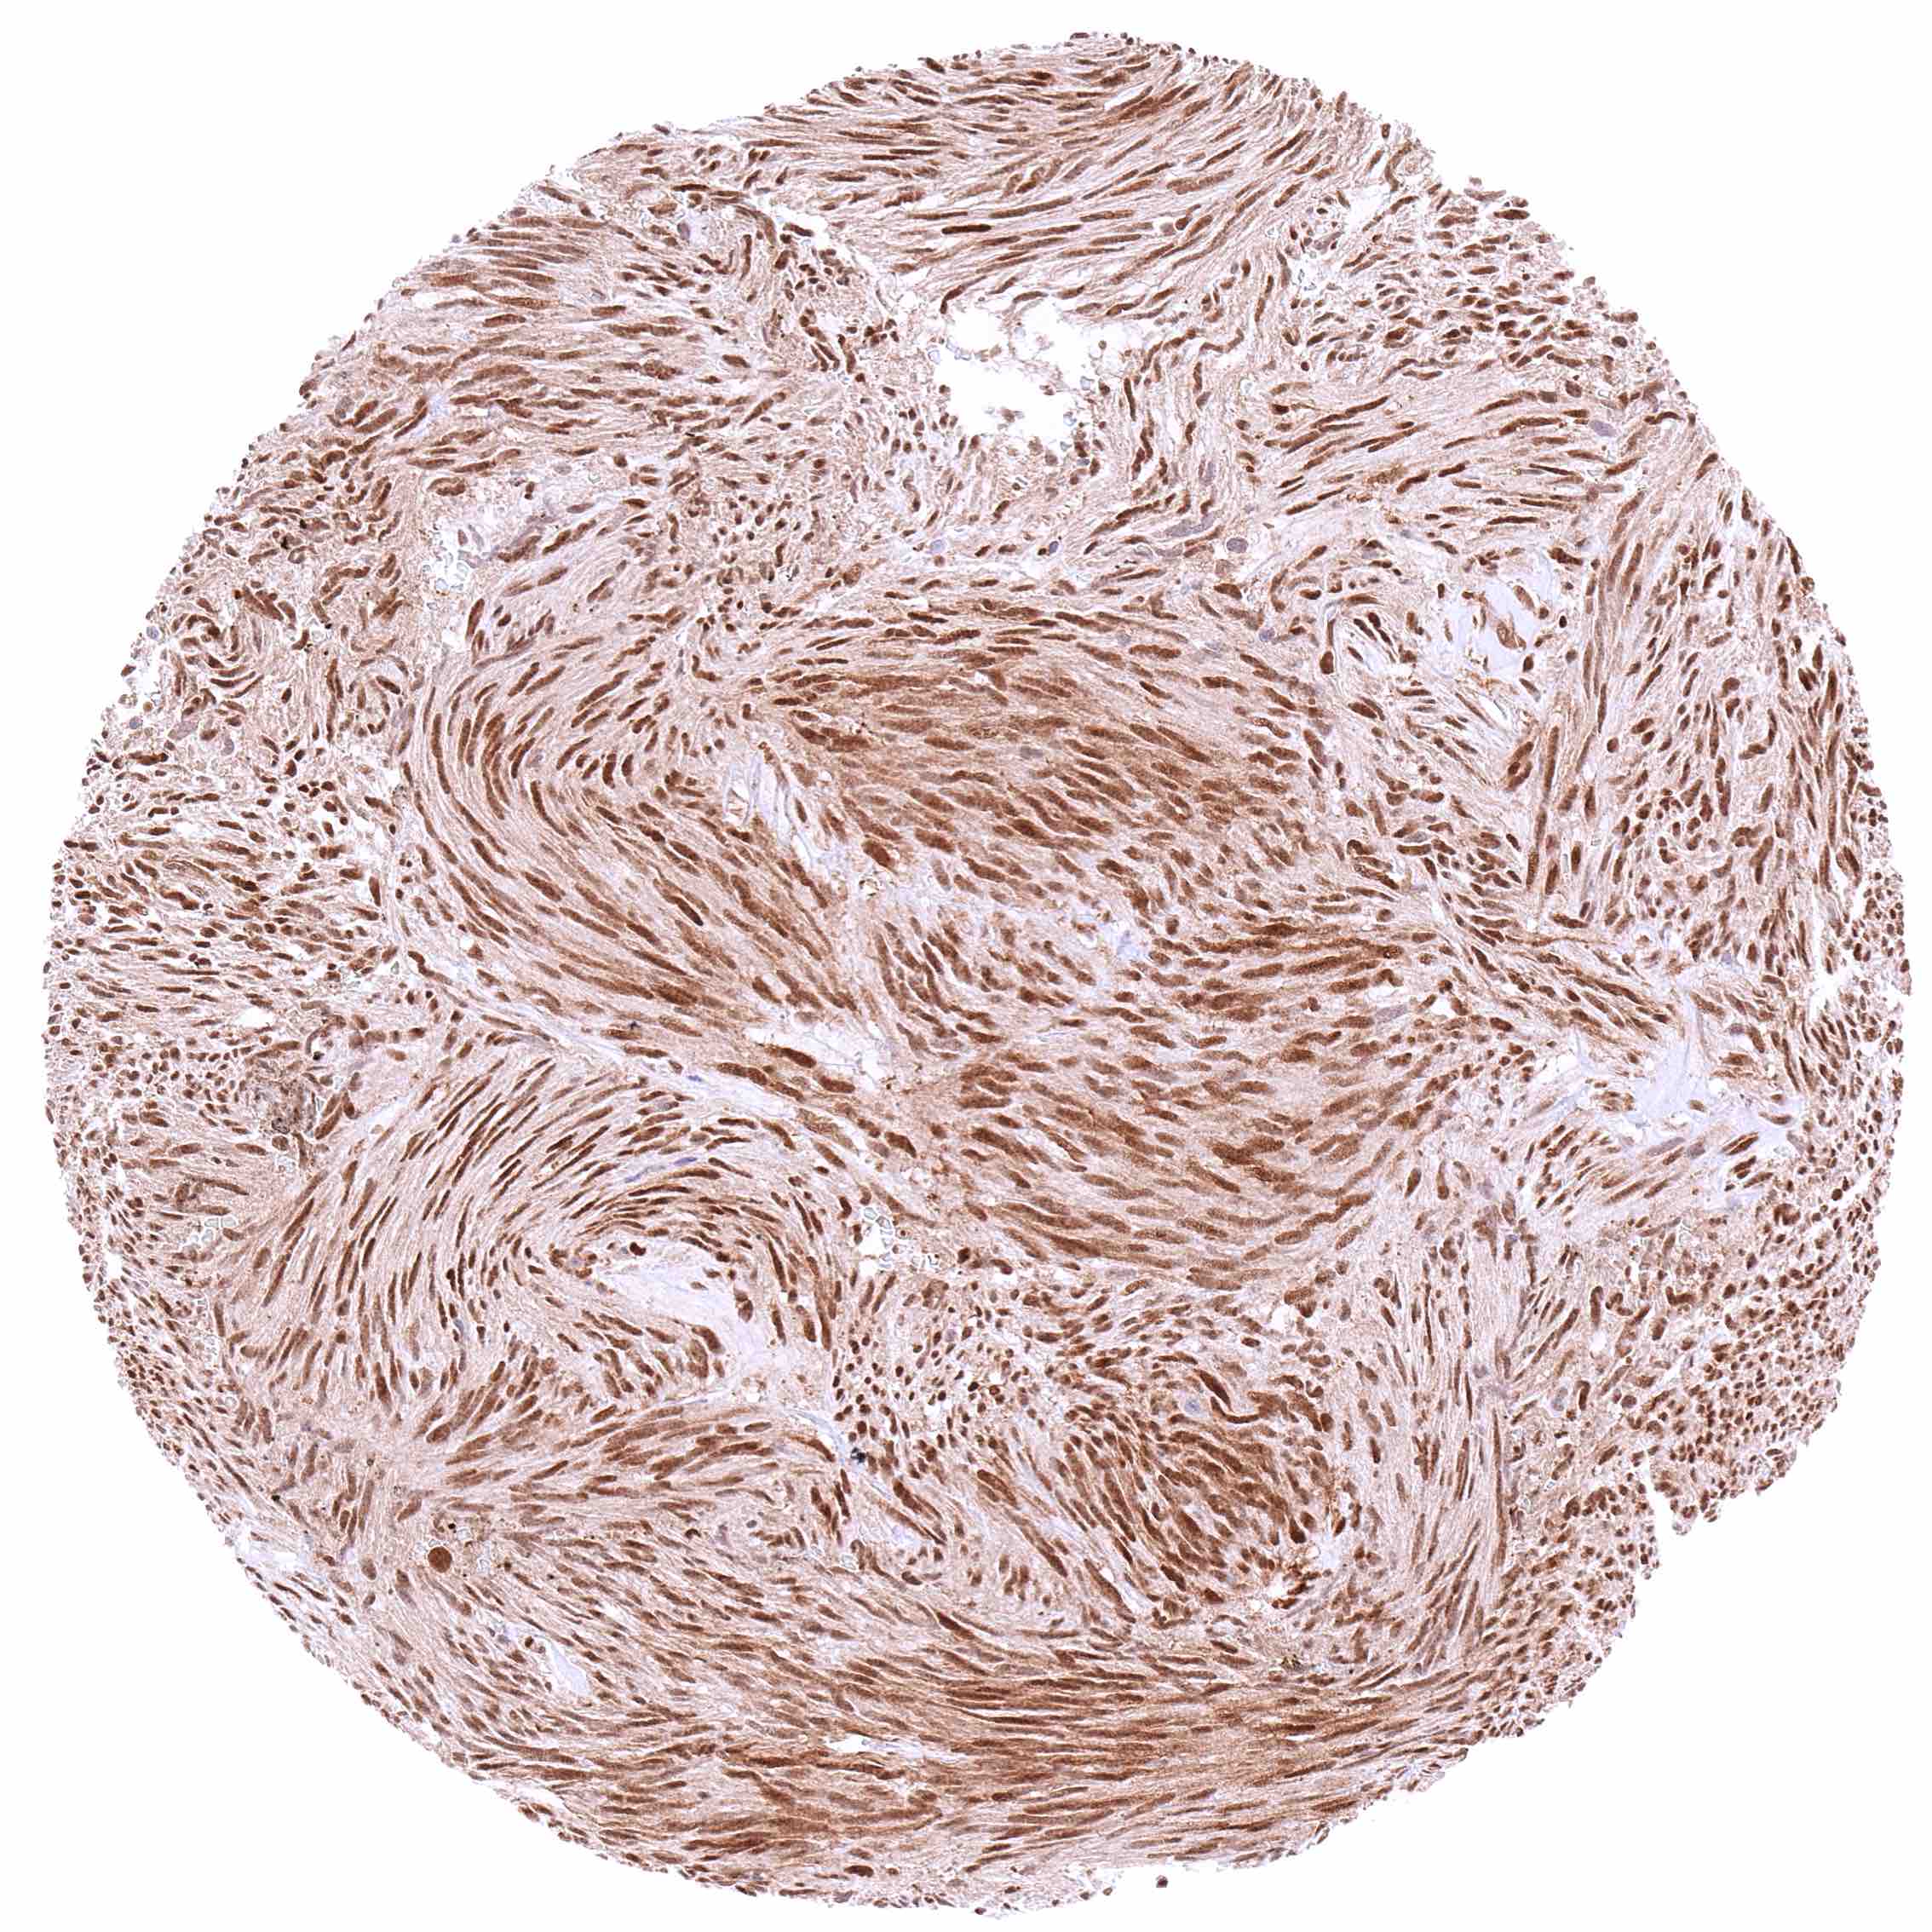

Stomach – Gastrointestinal stromal tumor (GIST) with a distinct nuclear and cytoplasmic p27 staining of all tumor cells.